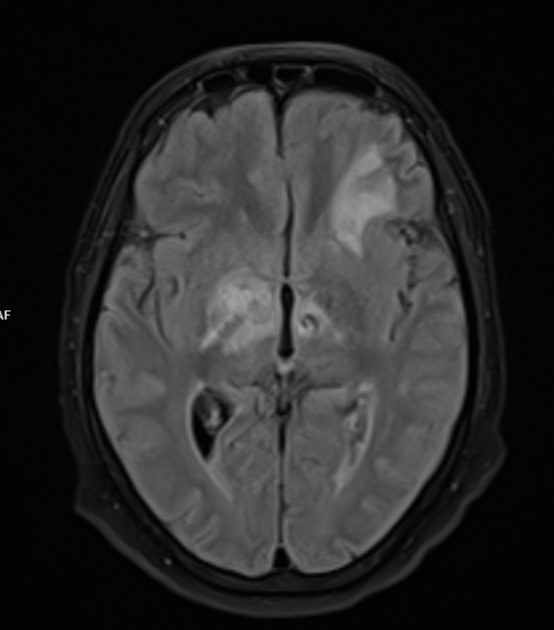

The patient in question presented to the emergency department following a series of new-onset seizures and alterations in mental status. Although his symptoms first appeared to be linked to diabetic ketoacidosis and various metabolic derangements, his condition rapidly deteriorated to the point where he entered status epilepticus—an incredibly overwhelming situation requiring immediate, advanced intervention.

Not only did the patient exhibit signs of hypertriglyceridemia, elevated lactate levels, and metabolic acidosis, but his case also raised critical questions about the source of his underlying condition. After extensive workup including a lumbar puncture and the use of a meningoencephalitis PCR panel, the patient was diagnosed with Listeria monocytogenes infection—a pathogen that typically represents a twisted detail hidden within the broader narrative of central nervous system infections.